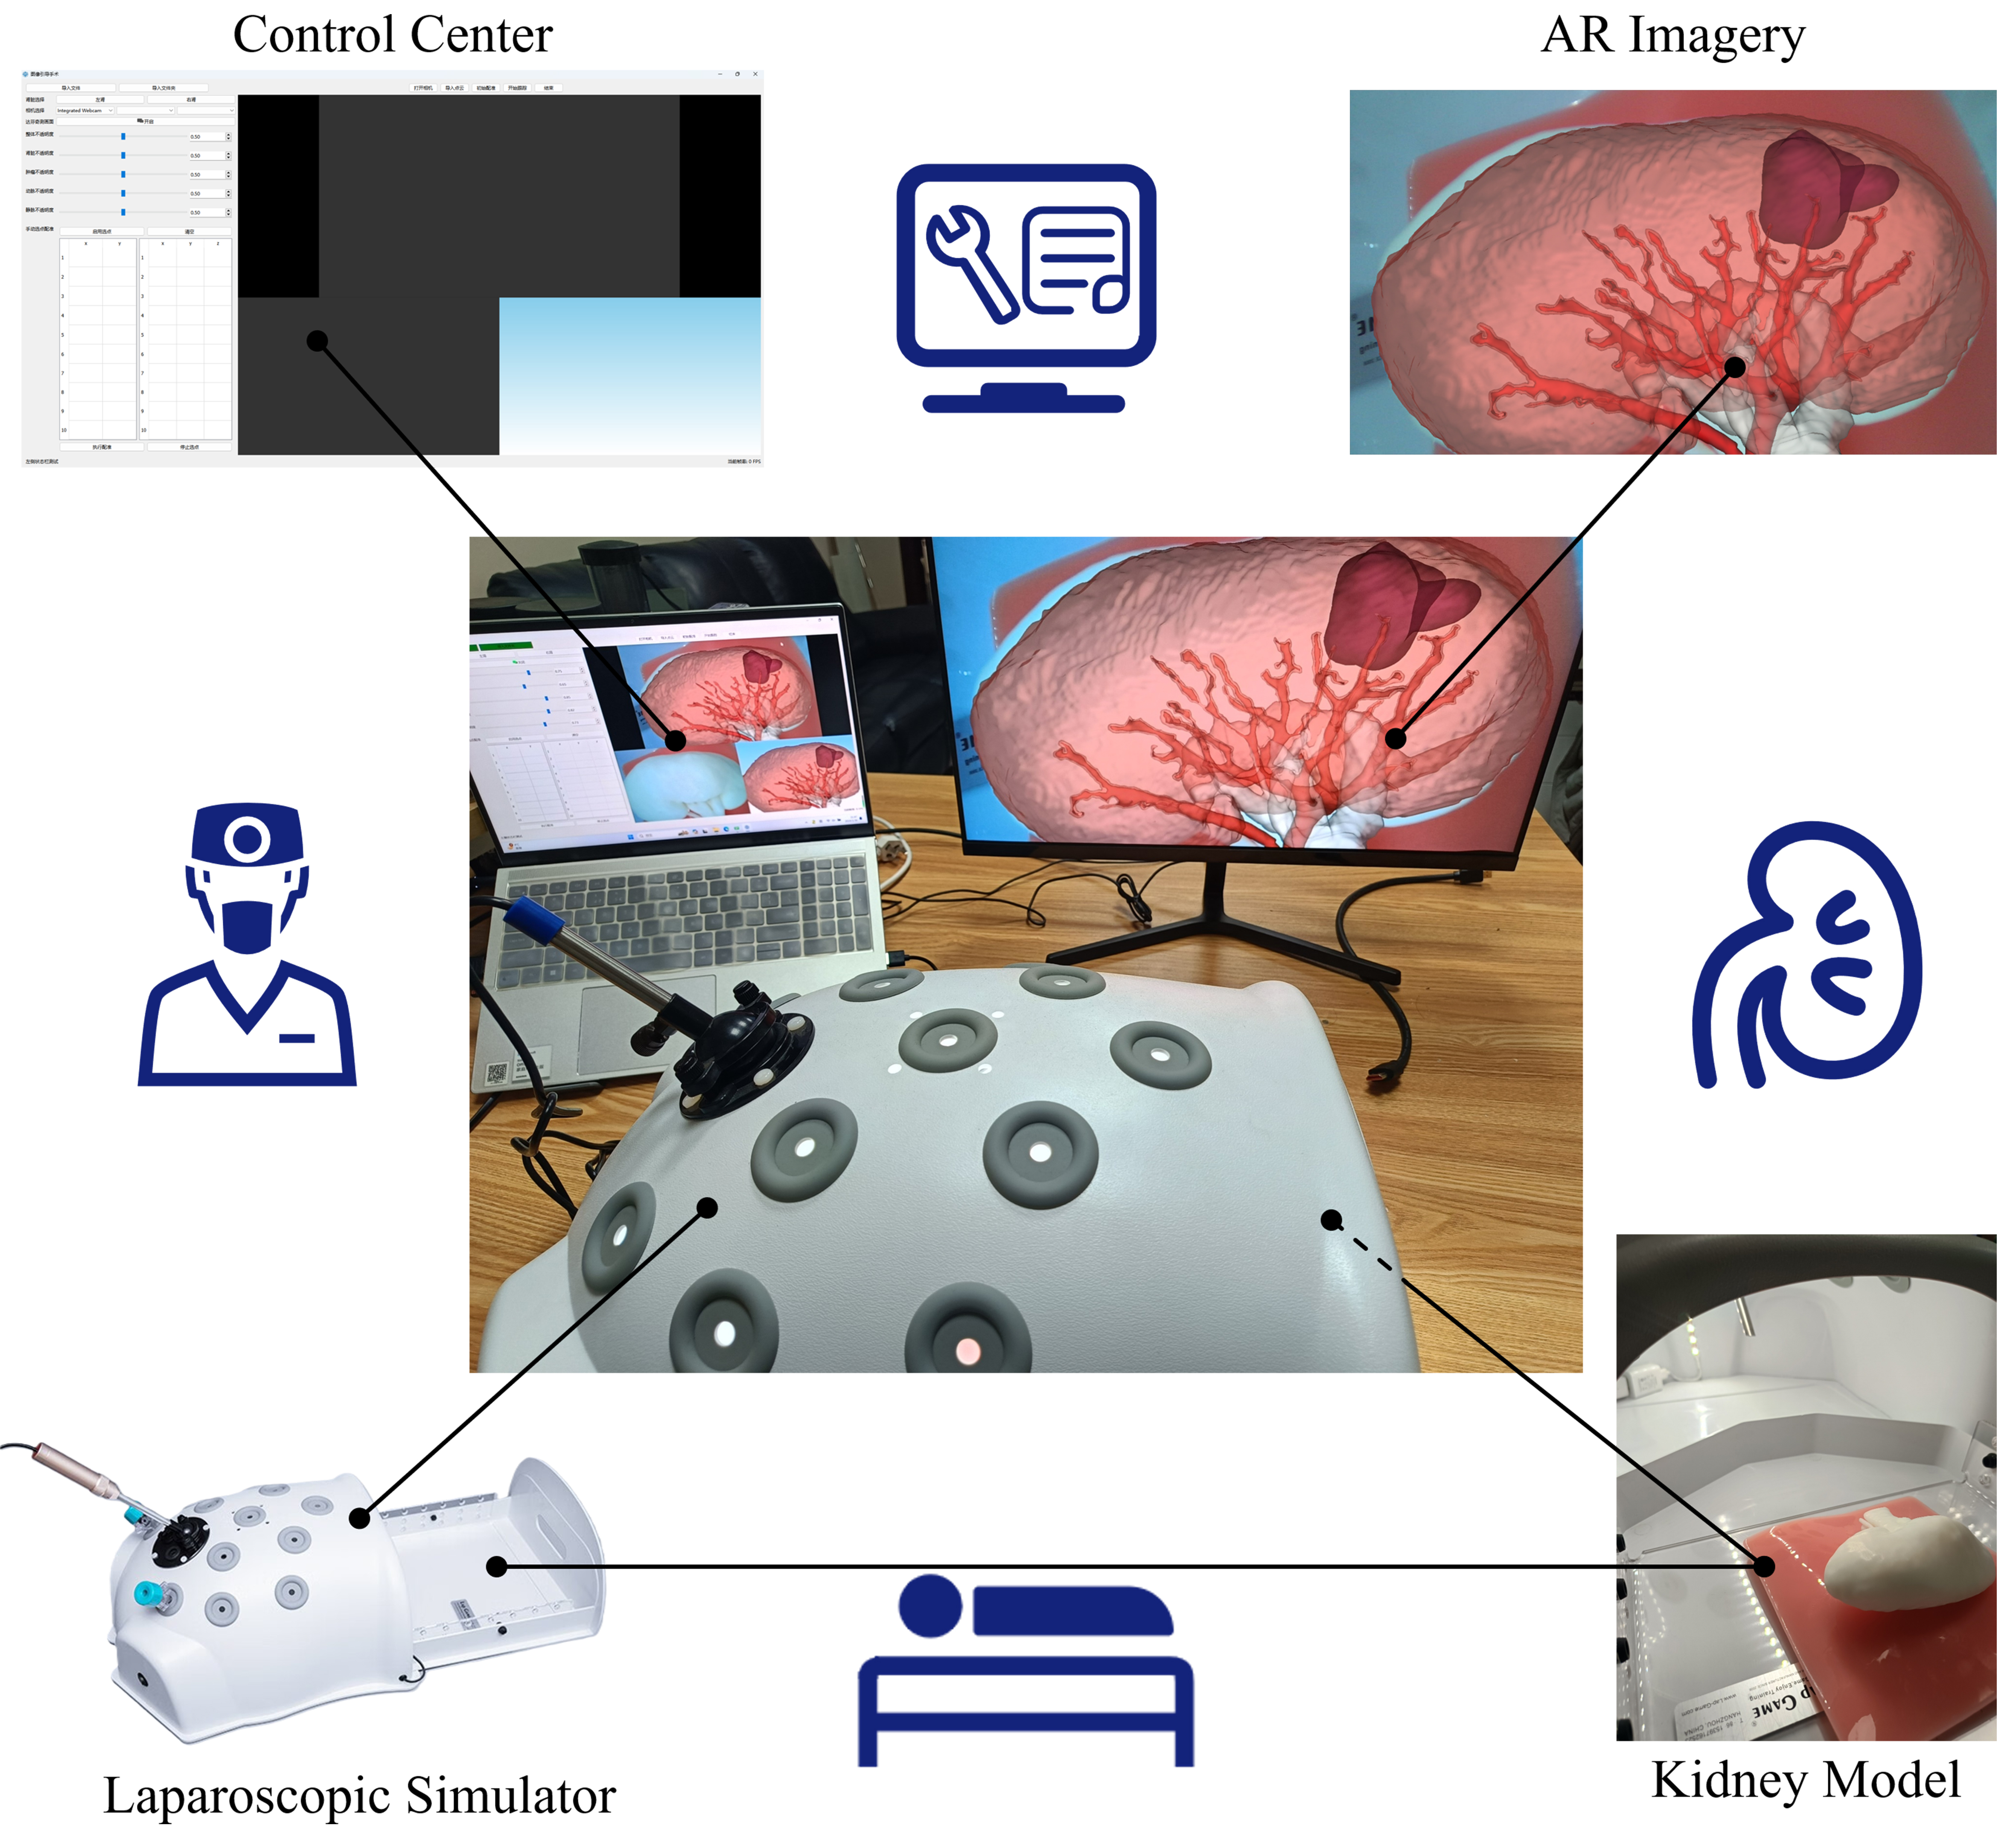

With the help of the network proposed in this article, we can quickly segment medical images. This network not only shortens the segmentation time to within 30 s, but also has very clear edges such as arteries and veins, which is very important for clinical diagnosis. Taking the partial nephrectomy as an example, we can take CTA image of the patient’s kidney again shortly before the surgery and combine the segmentation results with other former preoperative diagnoses to guide the surgical implementation.

In addition, we also proposed an AR-guided intraoperative localization framework for laparoscopic partial nephrectomy, as shown in Figure 10. Using the segmentation results to reconstruct the kidney, and utilizing manual initial point selection and video point tracking techniques to overlay the kidney reconstruction model with intraoperative images through PnP algorithm, an initial registration error of approximately

Figure 10. Schematic diagram of AR guidance system for laparoscopic partial nephrectomy. AR: Augmented reality.